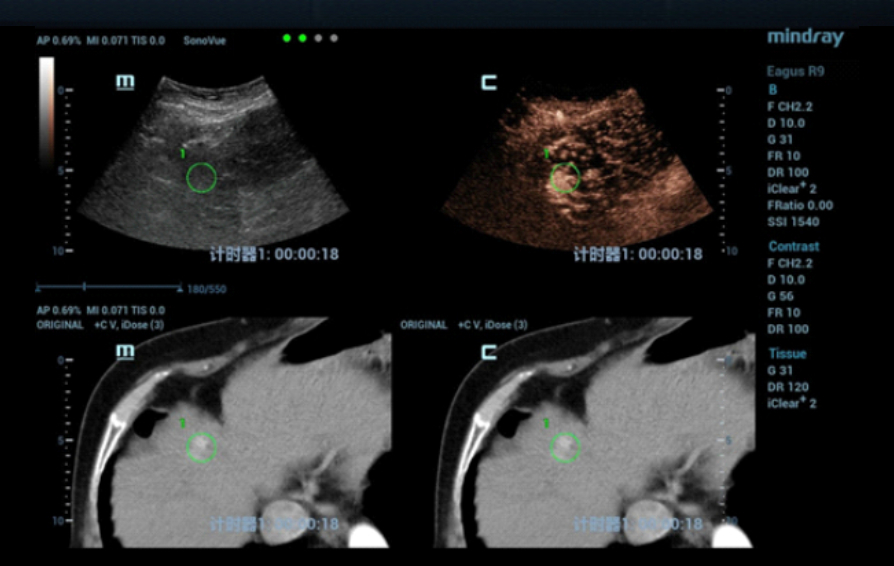

The patient was scheduled for ultrasound-guided microwave ablation (MWA), however, as the lesion could not be seen on conventional ultrasound, fusion imaging combining ultrasound imaging and contrast-enhanced CT (Clip 1, Figs. 4-7) was used to ensure accurate positioning of the microwave antenna.